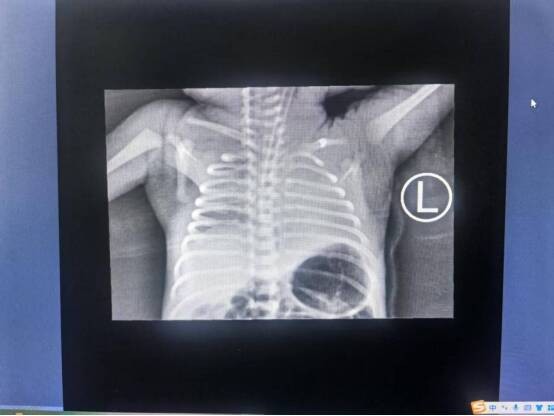

完善相关检查后明确患儿为急性呼吸窘迫综合征(NRDS)、肺出血。据新生儿科刘少华主任介绍,新生儿呼吸窘迫综合征(NRDS)是早产儿,尤其是极早和中期早产儿发病和死亡的主要原因,如合并反复肺出血死亡率极高(通常在50%-70%),其病理核心是肺表面活性物质(PS)的缺乏或不足、缺氧、感染。近年来,研究发现晚期早产儿NRDS的发病率及严重程度不容忽视,且常因肺结构相对更成熟而掩盖其潜在的严重性。

(患儿肺部情况)

面对这个体重微弱、呼吸艰难的小生命,科室制定了周密的治疗方案,包括气道精细管理、肺保护性通气策略及严格的液体平衡控制。在长达60天的救治中,医护人员日夜守护,像对待自己的孩子一样悉心照护。